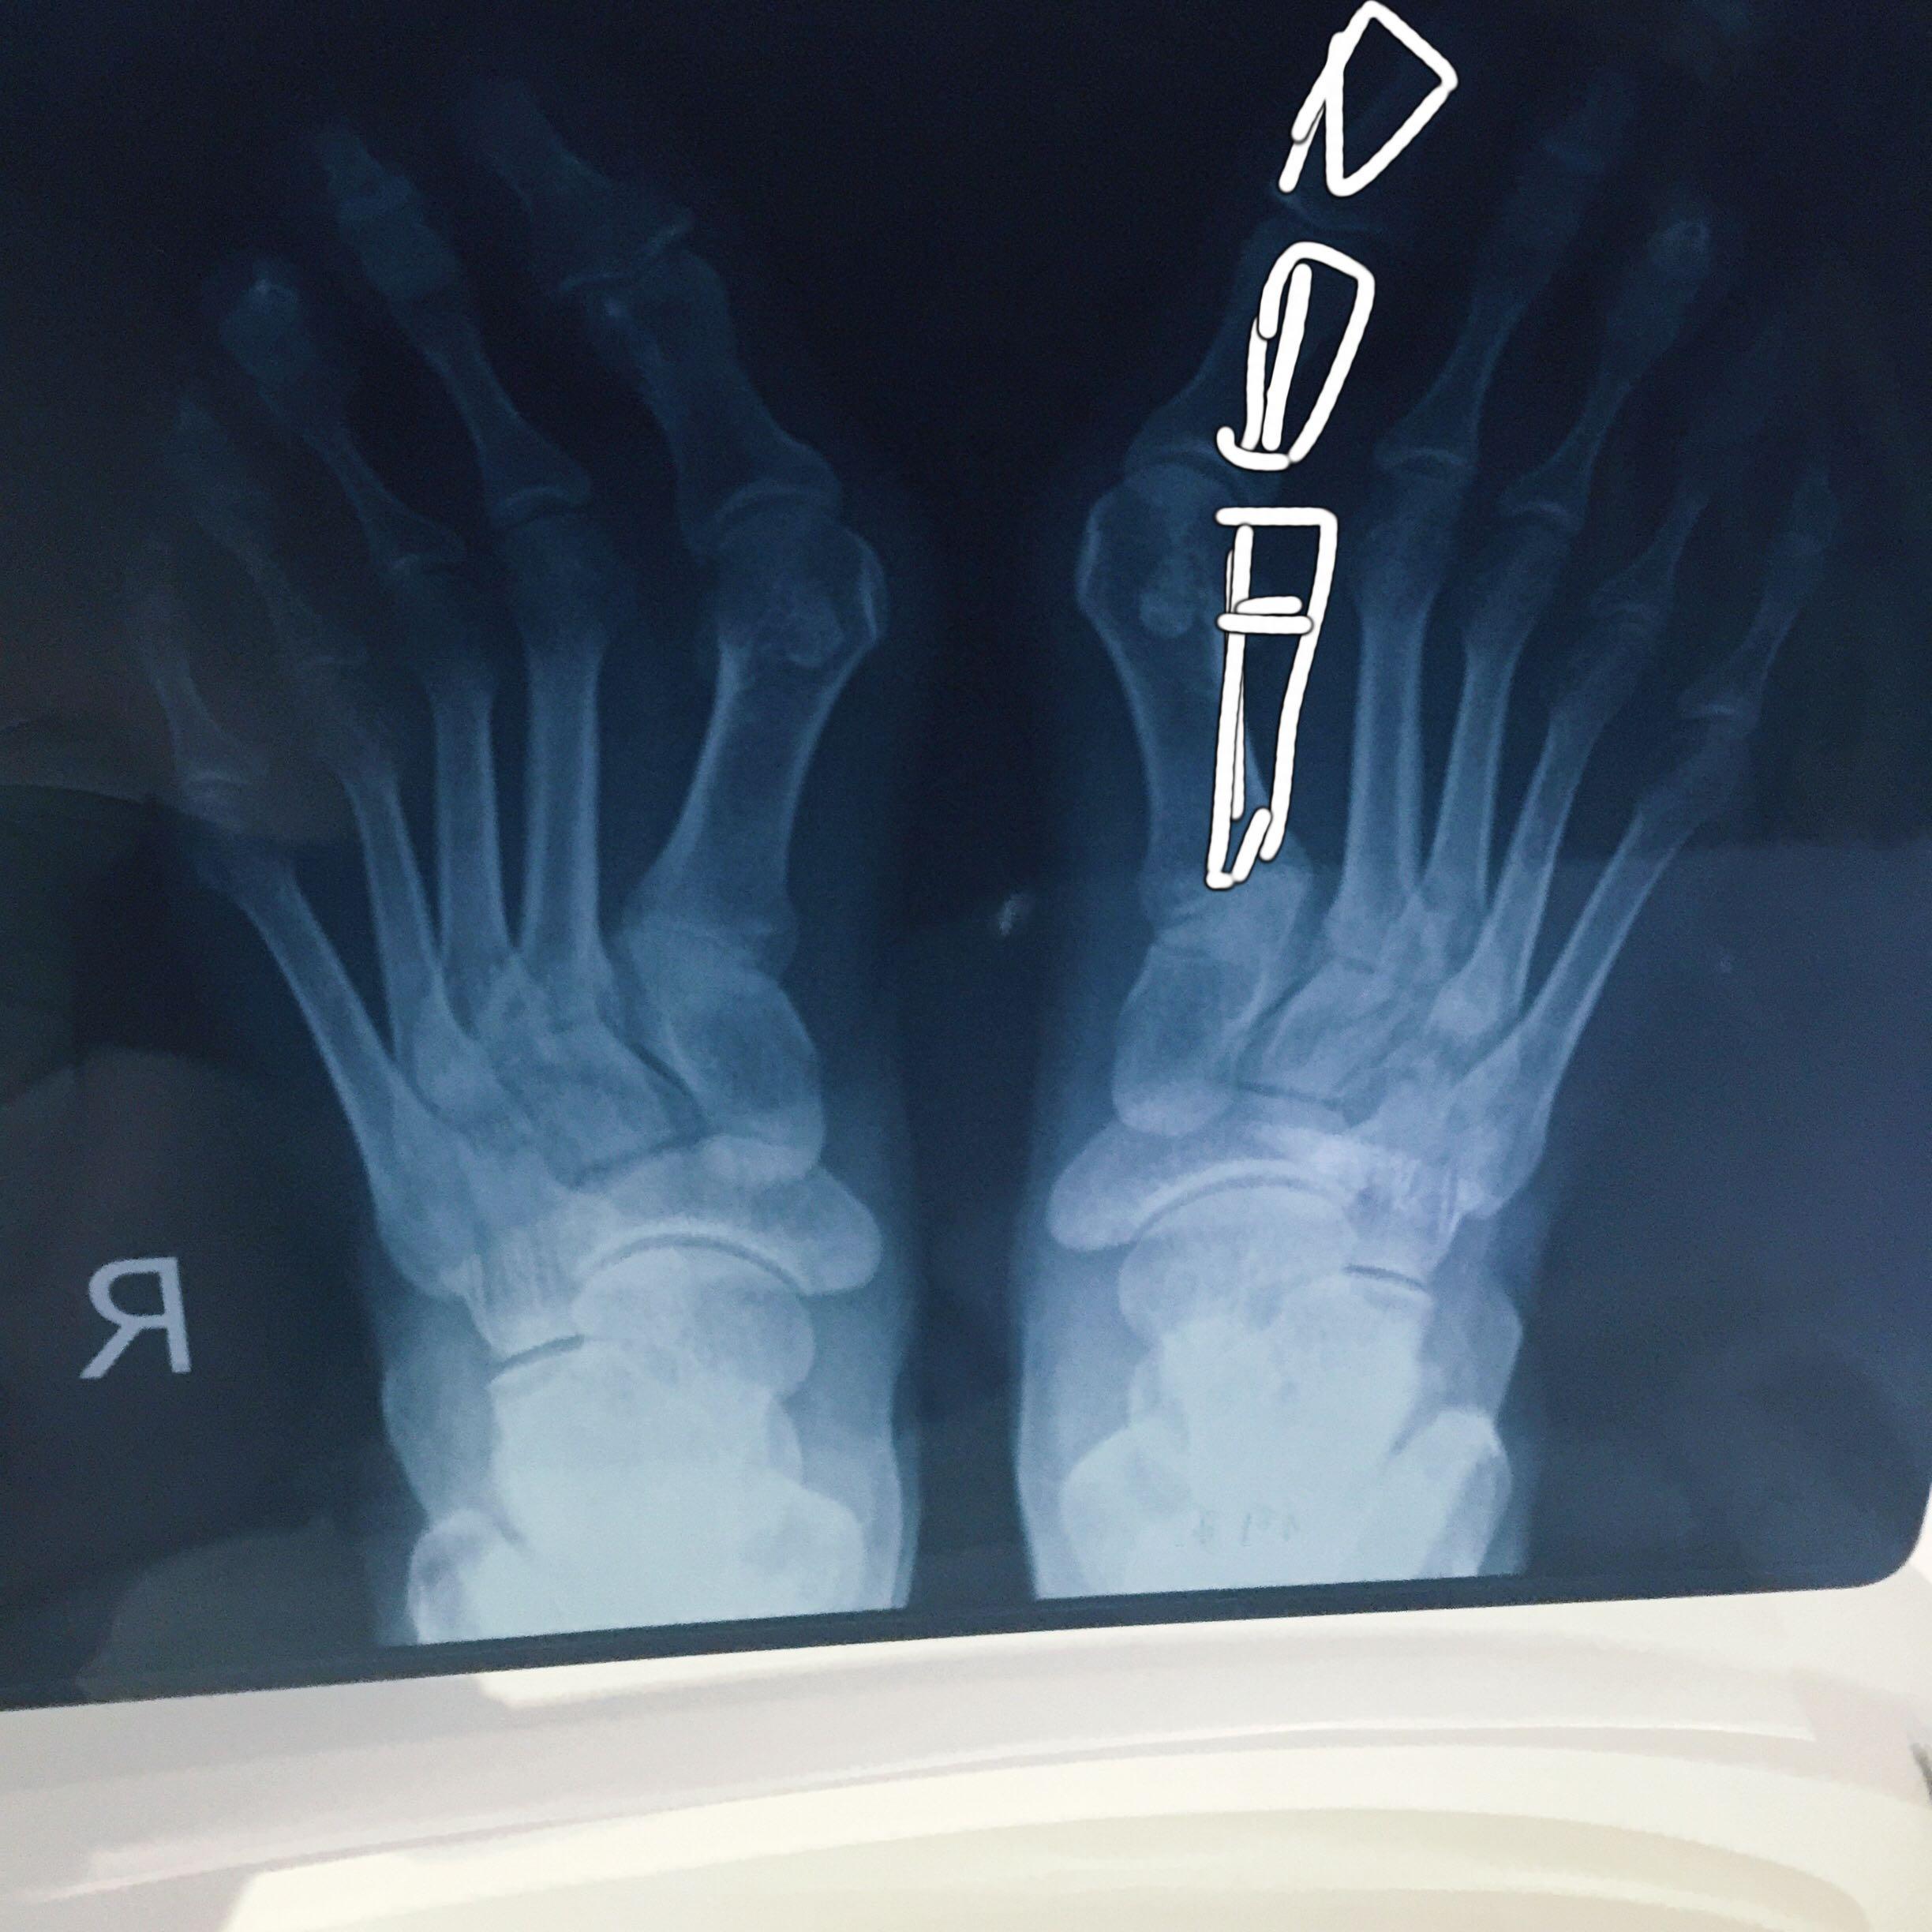

双足拇外翻畸形

图片尺寸2048x1536